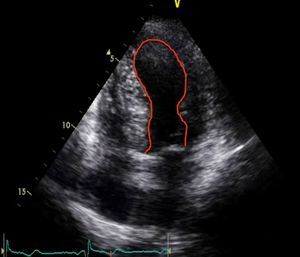

When she went to the ED with chest pain of eight hours’ duration she was hemodynamically stable with no signs of heart failure. The ECG showed sinus rhythm with ST-segment elevation in DI and aVL and ST-segment depression in DIII and aVF (Figure 1). Transthoracic echocardiography performed in the ED showed akinesia with dilatation of the apex and the mid-apical segments of the left ventricular (LV) wall, with no pericardial effusion (Figure 2).